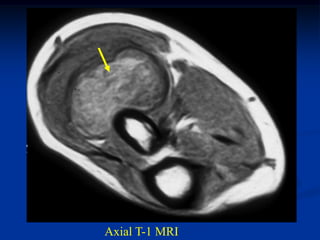

Case #1191

24 year female with

angiolipoma anterior

thigh

Sagittal T-1 MRI

Axial T-1 MRI

Coronal T-2 MRI

Sagittal gad

contrast MRI

Case #1191 24 yearfemale with angiolipoma anterior thigh Sagittal T-1 MRI

• 90.

• 91.

• 92.